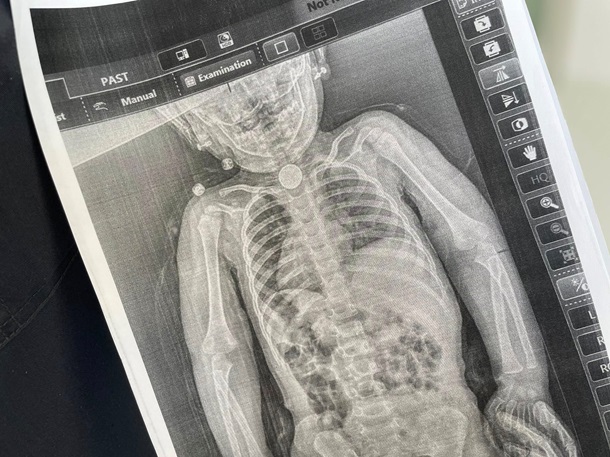

Лише на початку весни, після повторного звернення, батьки наполягли на додатковому обстеженні. Рентген показав сторонній предмет у стравоході, а ендоскопія підтвердила: у зоні фізіологічного звуження застрягла кругла літієва батарейка діаметром близько 2,5 см. Навколо неї вже утворилися набряк і пошкодження слизової оболонки.

З огляду на складність ситуації дитину терміново госпіталізували до Дитяча лікарня Святого Миколая. За допомогою ларингоскопа та спеціальних інструментів хірурги змогли безпечно видалити небезпечний предмет.